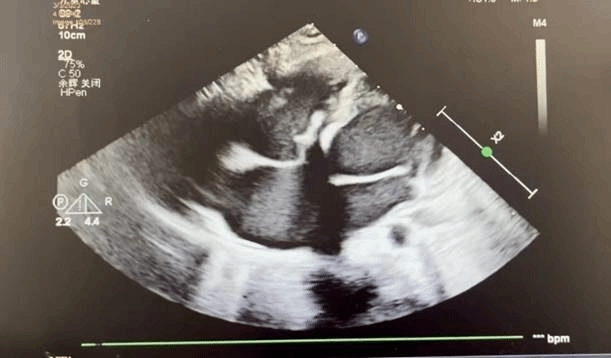

术后超声

他强调,全降解封堵器在透视下完全不显影,所以术中释放封堵器需全程在超声指导下进行,这需要手术团队具有高超的超声水平,超声医师与介入术者之间配合默契极为重要。从操作更安全的角度出发,术中结合超声引导与X线透视行介入封堵具有重要意义,这样不仅可大大减少X线透视对患者及医生的伤害,同时亦可凭借超声实时监测的优势为术中封堵器精准定位及释放等提供有效指导。